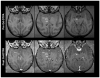

It has been suggested, based on rodent studies, that levodopa (L-dopa) induced dyskinesia is associated with a disrupted blood-brain barrier (BBB). We have investigated BBB integrity with in vivo neuroimaging techniques in six 1-methyl-4-phenyl-1,2,3,6-tetrahydropyridine (MPTP) lesioned primates exhibiting L-dopa-induced dyskinesia. Magnetic resonance imaging (MRI) performed before and after injection of Gadolinium-diethylenetriamine pentaacetic acid (Gd-DTPA) revealed an intact BBB in the basal ganglia showing that l-dopa-induced dyskinesia is not associated with a disrupted BBB in this model.